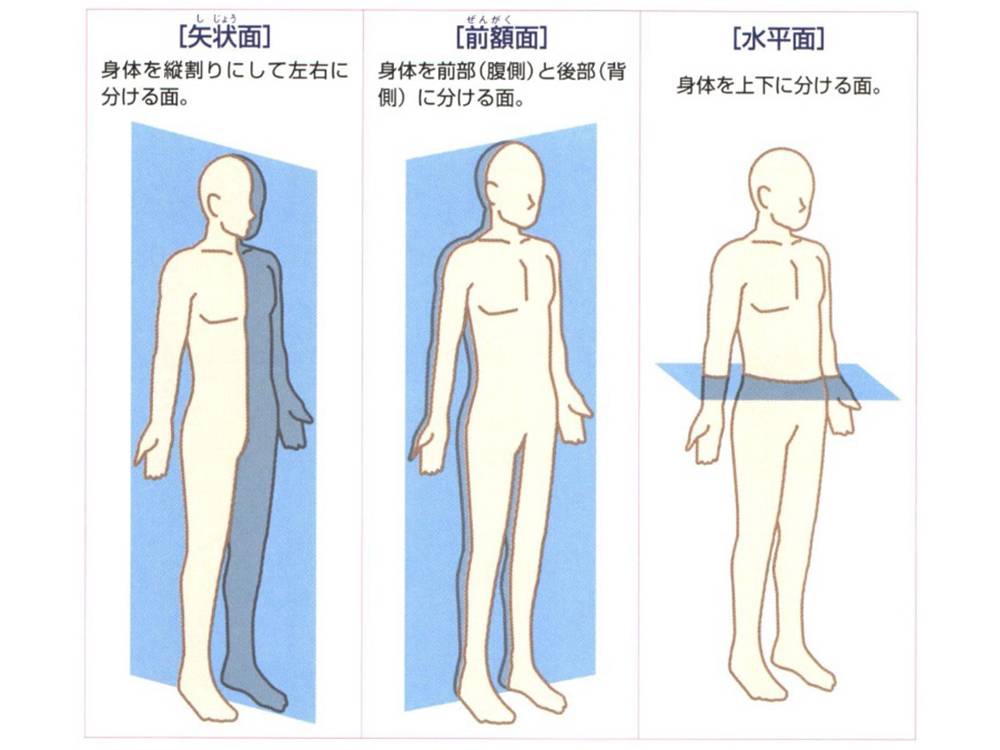

矢状面、冠状面、水平面が分からない? これで完全理解!! 身体の方向をあらわす3つの基準面 矢状面、冠状面、水平面 、本当に理解している?ここって、結構間違えやすい部分だよね。 なので、今回は「矢状面 正中面 」「冠状面」「水平面」のそれぞれの覚え方を。

身体の方向をあらわす3つの基準面 矢状面 正中面 、冠状面、水平面 のイラスト🎨 フリー素材 看護roo! カンゴルー。

矢状面、冠状面、水平面が分からない? これで完全理解!! 身体の方向をあらわす3つの基準面 矢状面、冠状面、水平面 、本当に理解している?ここって、結構間違えやすい部分だよね。 なので、今回は「矢状面 正中面 」「冠状面」「水平面」のそれぞれの覚え方を。

身体の方向をあらわす3つの基準面 矢状面 正中面 、冠状面、水平面 のイラスト🎨 フリー素材 看護roo! カンゴルー。

人体の基準面で矢状面 と 冠状面 がごっちゃになる人へ。 このイラストのイメージがあると記憶に残ります。

矢状面、冠状面、水平面が分からない? これで完全理解!! 身体の方向をあらわす3つの基準面 矢状面、冠状面、水平面 、本当に理解している?ここって、結構間違えやすい部分だよね。 なので、今回は「矢状面 正中面 」「冠状面」「水平面」のそれぞれの覚え方を。

矢状面、冠状面、水平面が分からない? これで完全理解!! 身体の方向をあらわす3つの基準面 矢状面、冠状面、水平面 、本当に理解している?ここって、結構間違えやすい部分だよね。 なので、今回は「矢状面 正中面 」「冠状面」「水平面」のそれぞれの覚え方を。